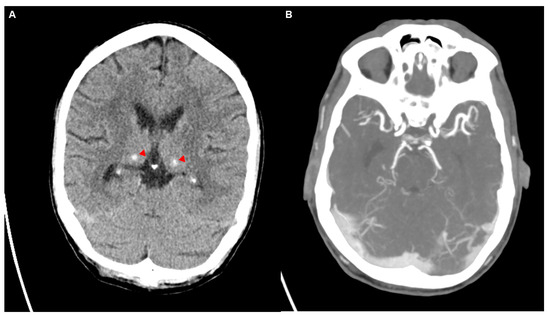

Figure 2.

The initial non-contrast CT scan of the head (A) revealed cerebrospinal fluid spaces that were age-appropriate, with no evidence of mass effect or intracranial hemorrhage. There were no signs of acute ischemic changes. Hyperdensities observed bilaterally in the thalami were consistent with calcifications, which were newly noted compared to prior imaging from 2022 (two years before). Additionally, defects that were previously observed in the right temporal lobe on imaging two years earlier were noted again, accompanied by ex vacuo dilation of the right temporal horn of the lateral ventricle. The calcifications of the basal ganglia, although newly observed, were considered incidental and had no clinical significance, consistent with previous reports of age-related or physiological calcifications in the basal ganglia and thalamus [4]. A CT angiography (CTA) (B) of the extra- and intracranial vessels in a mixed arterial and venous phase. There was a calcified plaque in the left vertebral artery, besides that the CTA showed normal arterial and venous structures without any evidence of vascular malformations, stenoses, or aneurysms. There are no signs of thrombosis or other vascular abnormalities, with intact and well-defined vessels throughout the visible cerebral vasculature.